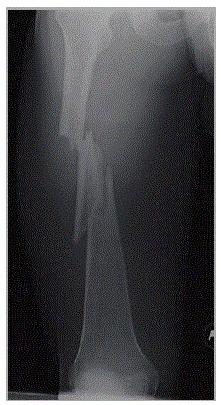

Homem, 23 anos de idade, vítima de queda de motocicleta há 2 horas. Sem outras alterações ao exame físico, exceto a fratura isolada de fêmur direito. Sem lesões vasculonervosas ou de partes moles (figura a seguir).

Qual é o melhor tratamento?